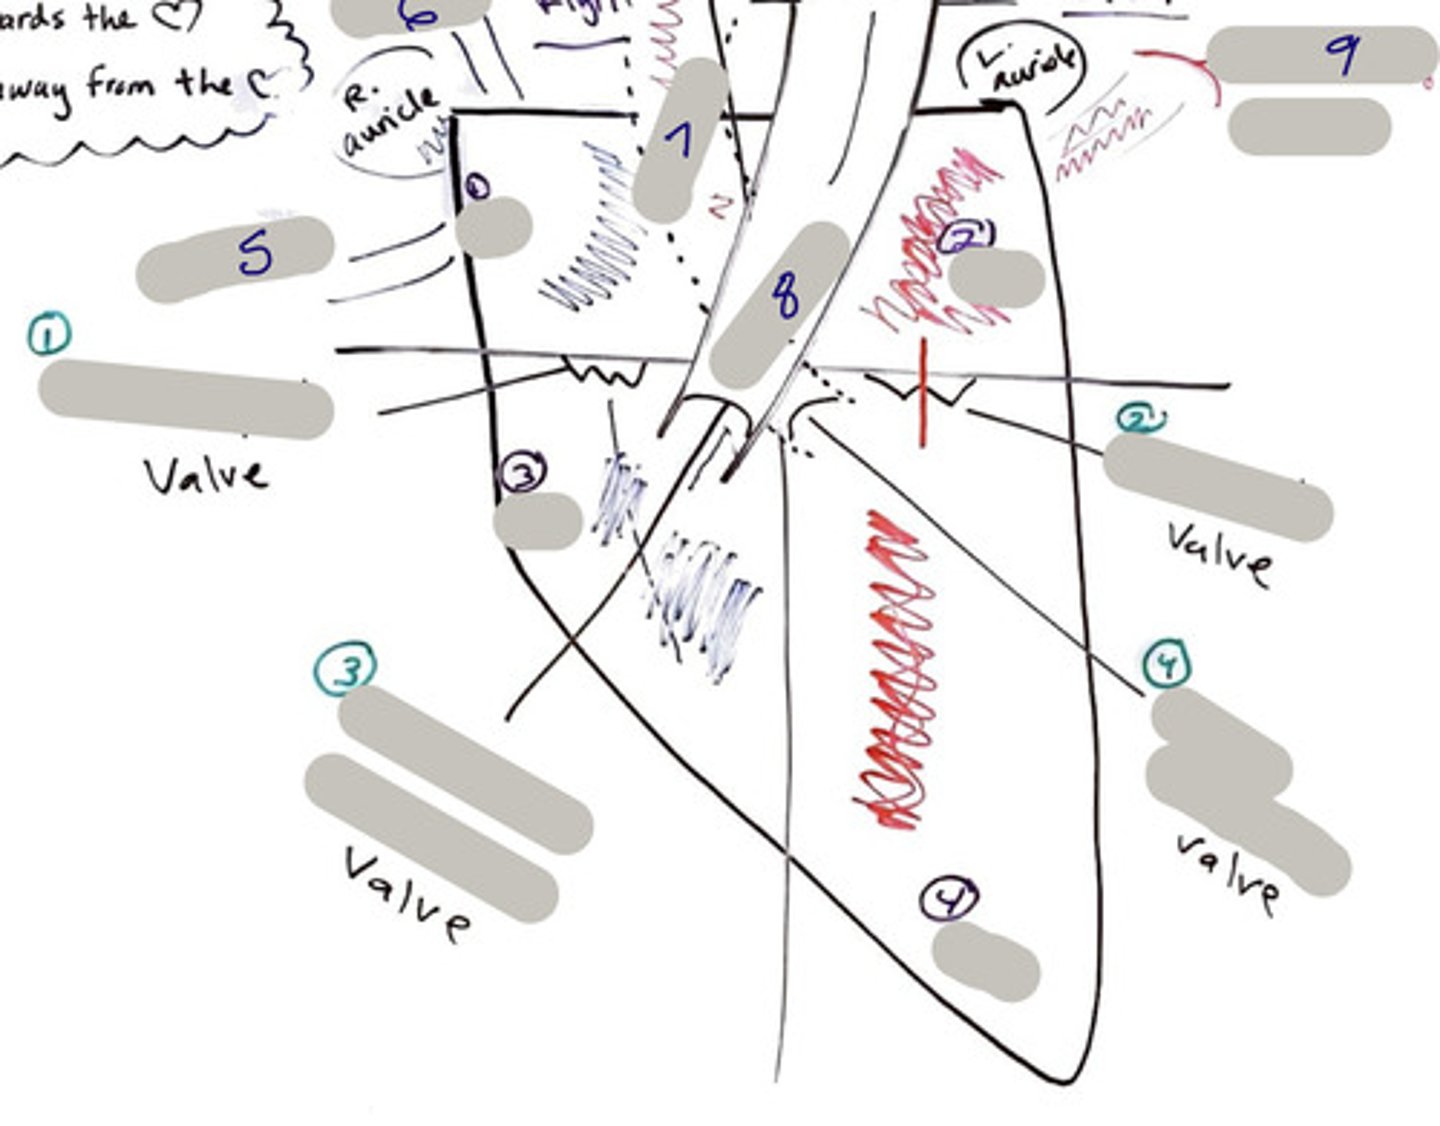

Tricuspid Valve (Right Atrioventricular Valve)

1-valve

Bicuspid valve (Left Atrioventricular Valve)

2-valve

Pulmonary Semilunar Valve

3-valve

Aortic Semilunar Valve

4-valve

Right Atrium

1-chamber

Left Atrium

2-chamber

Right Ventricle

3-chamber

Left Ventricle

4-chamber

Inferior Vena Cava

5-A vein that is the largest vein in the human body and returns blood to the right atrium of the heart from bodily parts below the diaphragm.

Superior Vena Cava

6-A vein that is the second largest vein in the human body and returns blood to the right atrium of the heart from the upper half of the body.

Aorta

7-The large arterial trunk that carries blood from the heart to be distributed by branch arteries through the body.

Pulmonary Trunk

8-carries blood from right ventricle to pulmonary arteries

Pulmonary veins

9-a vein carrying oxygenated blood from the lungs to the left atrium of the heart.